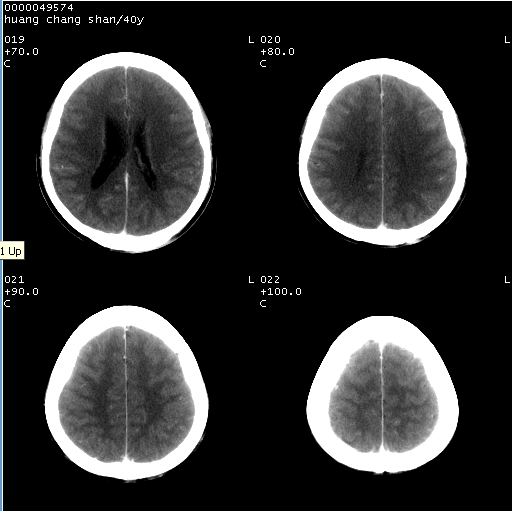

患者 m,40y。头痛,视力模糊,多饮多尿,性欲减退半年余。

行ct平扫+增强,图象如下:

2、ct表现:肿瘤呈类圆形,均匀略高密度,无囊变,无钙化。侧脑室有扩大。